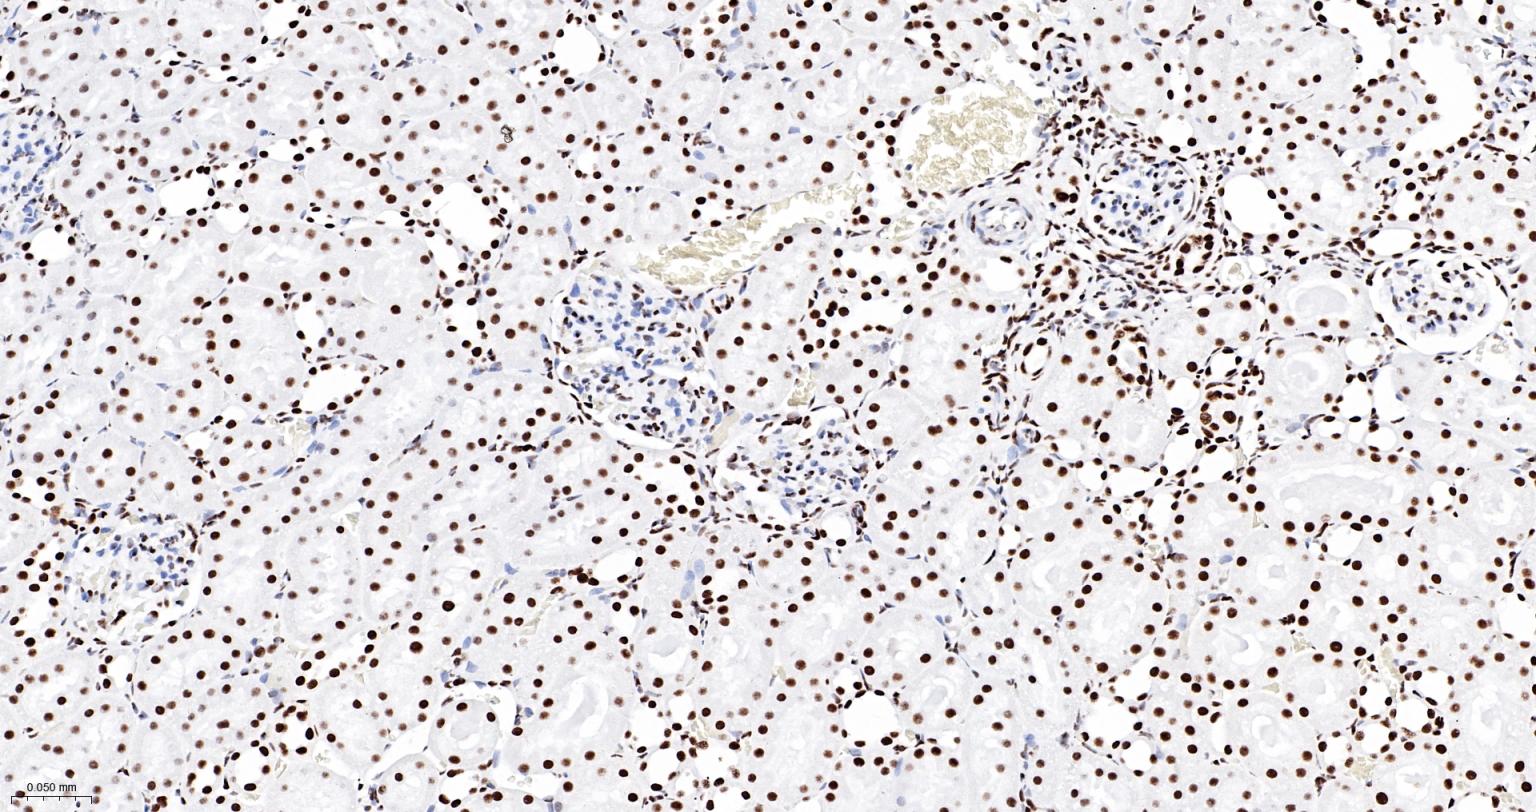

Paraformaldehyde-fixed, paraffin embedded Human Kidney; Antigen retrieval by boiling in sodium citrate buffer (pH6.0) for 15 min; The section was incubated with ARID1A Monoclonal Antibody, Unconjugated (bsm-61359R) at 1:200 overnight at 4°C, followed by conjugation to the bs-0295G-HRP and DAB (C-0010) staining.